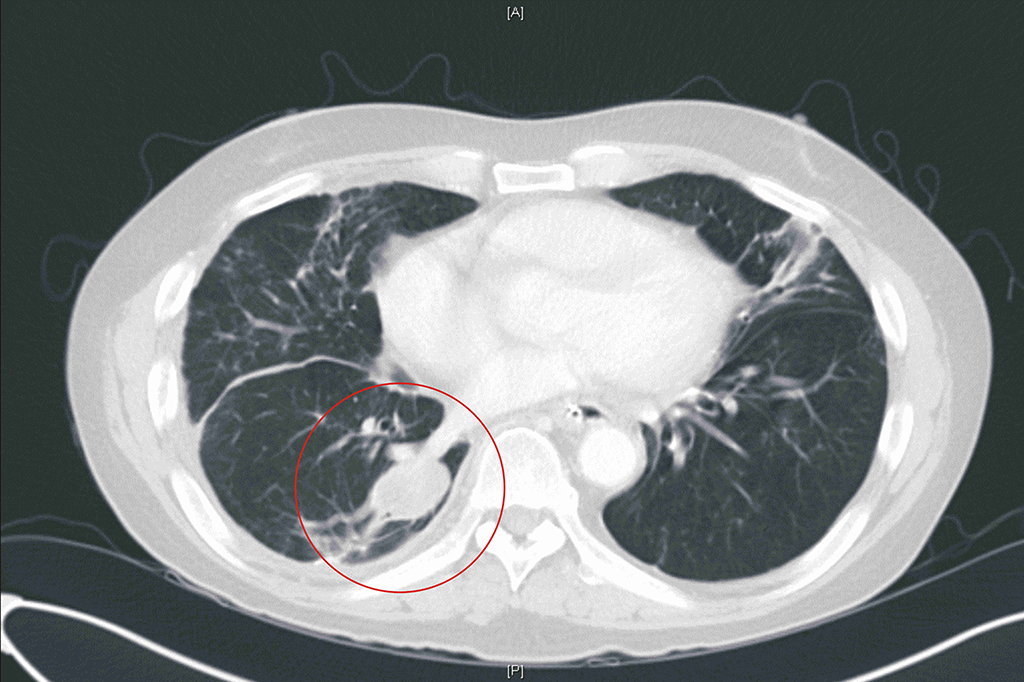

鄭雅夫醫師指出,一位52歲男性為因為罹患下咽癌合併多處轉移,經過化療及免疫治療後,仍然有右上肺及右下肺的腫瘤存在。患者於7個月前接受胸腔鏡右上肺及右下肺部分切除後腫瘤控制較穩定。此次再次發現右下肺長出一顆三公分的腫瘤,有鑑於病患的肺功能不佳,二次手術也容易沾黏較不合適,於是選擇了在複合式手術室中做微波肺部消融術治療,術後腫瘤消融狀況良好,病患也於觀察一天後即可出院,肺部消融術是一項針對不適合接受肺部切除術的良好替代選擇。

52歲男性患者,微波消融術前,右下肺一顆3公分腫瘤。

52歲男性患者,腫瘤經微波消融術而壞死。